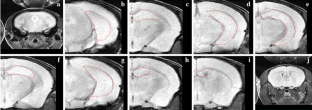

Fig. 3